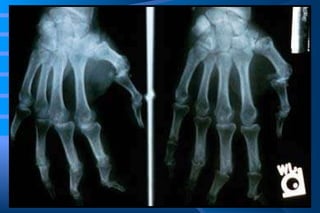

The characteristic deformity and soft tissue swelling associated with long-standing rheumatoid disease of the hands.

Rheumatoid Arthritis: Morphology Symmetric arthritis of small joints (proximal interphalangeal & metacarpophalangeal  Chronic synovitis, proliferation of synovial lining cells (villous projections) Subsynovial inflammatory cells   lymphoid nodules Pannus- highly vascularized, inflamed, reduplicated synovium Fibrosis & calcification   ankylosis Synovial fluid contains neutrophils

The inflammatory pannus causes FOCAL DESTRUCTION OF BONE. At the edges of the joint there is osteolytic destruction of bone. This phase is associated with joint deformity.